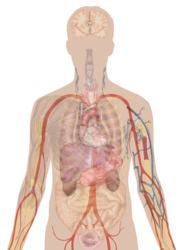

Human body diagramsMain article at: Human body diagrams Template location: Template:Human body diagrams How to derive an imageDerive directly from raster image with organsThe raster (.png format) images below have most commonly used organs already included, and text and lines can be added in almost any graphics editor. This is the easiest method, but does not leave any room for customizing what organs are shown.

Adding text and lines: Derive "from scratch"By this method, body diagrams can be derived by pasting organs into one of the "plain" body images shown below. This method requires a graphics editor that can handle transparent images, in order to avoid white squares around the organs when pasting onto the body image. Pictures of organs are found on the project's main page. These were originally adapted to fit the male shadow/silhouette.

Organs:

Derive by vector templateThe Vector templates below can be used to derive images with, for example, Inkscape. This is the method with the greatest potential. See Human body diagrams/Inkscape tutorial for a basic description in how to do this.

Examples of derived worksMore examples